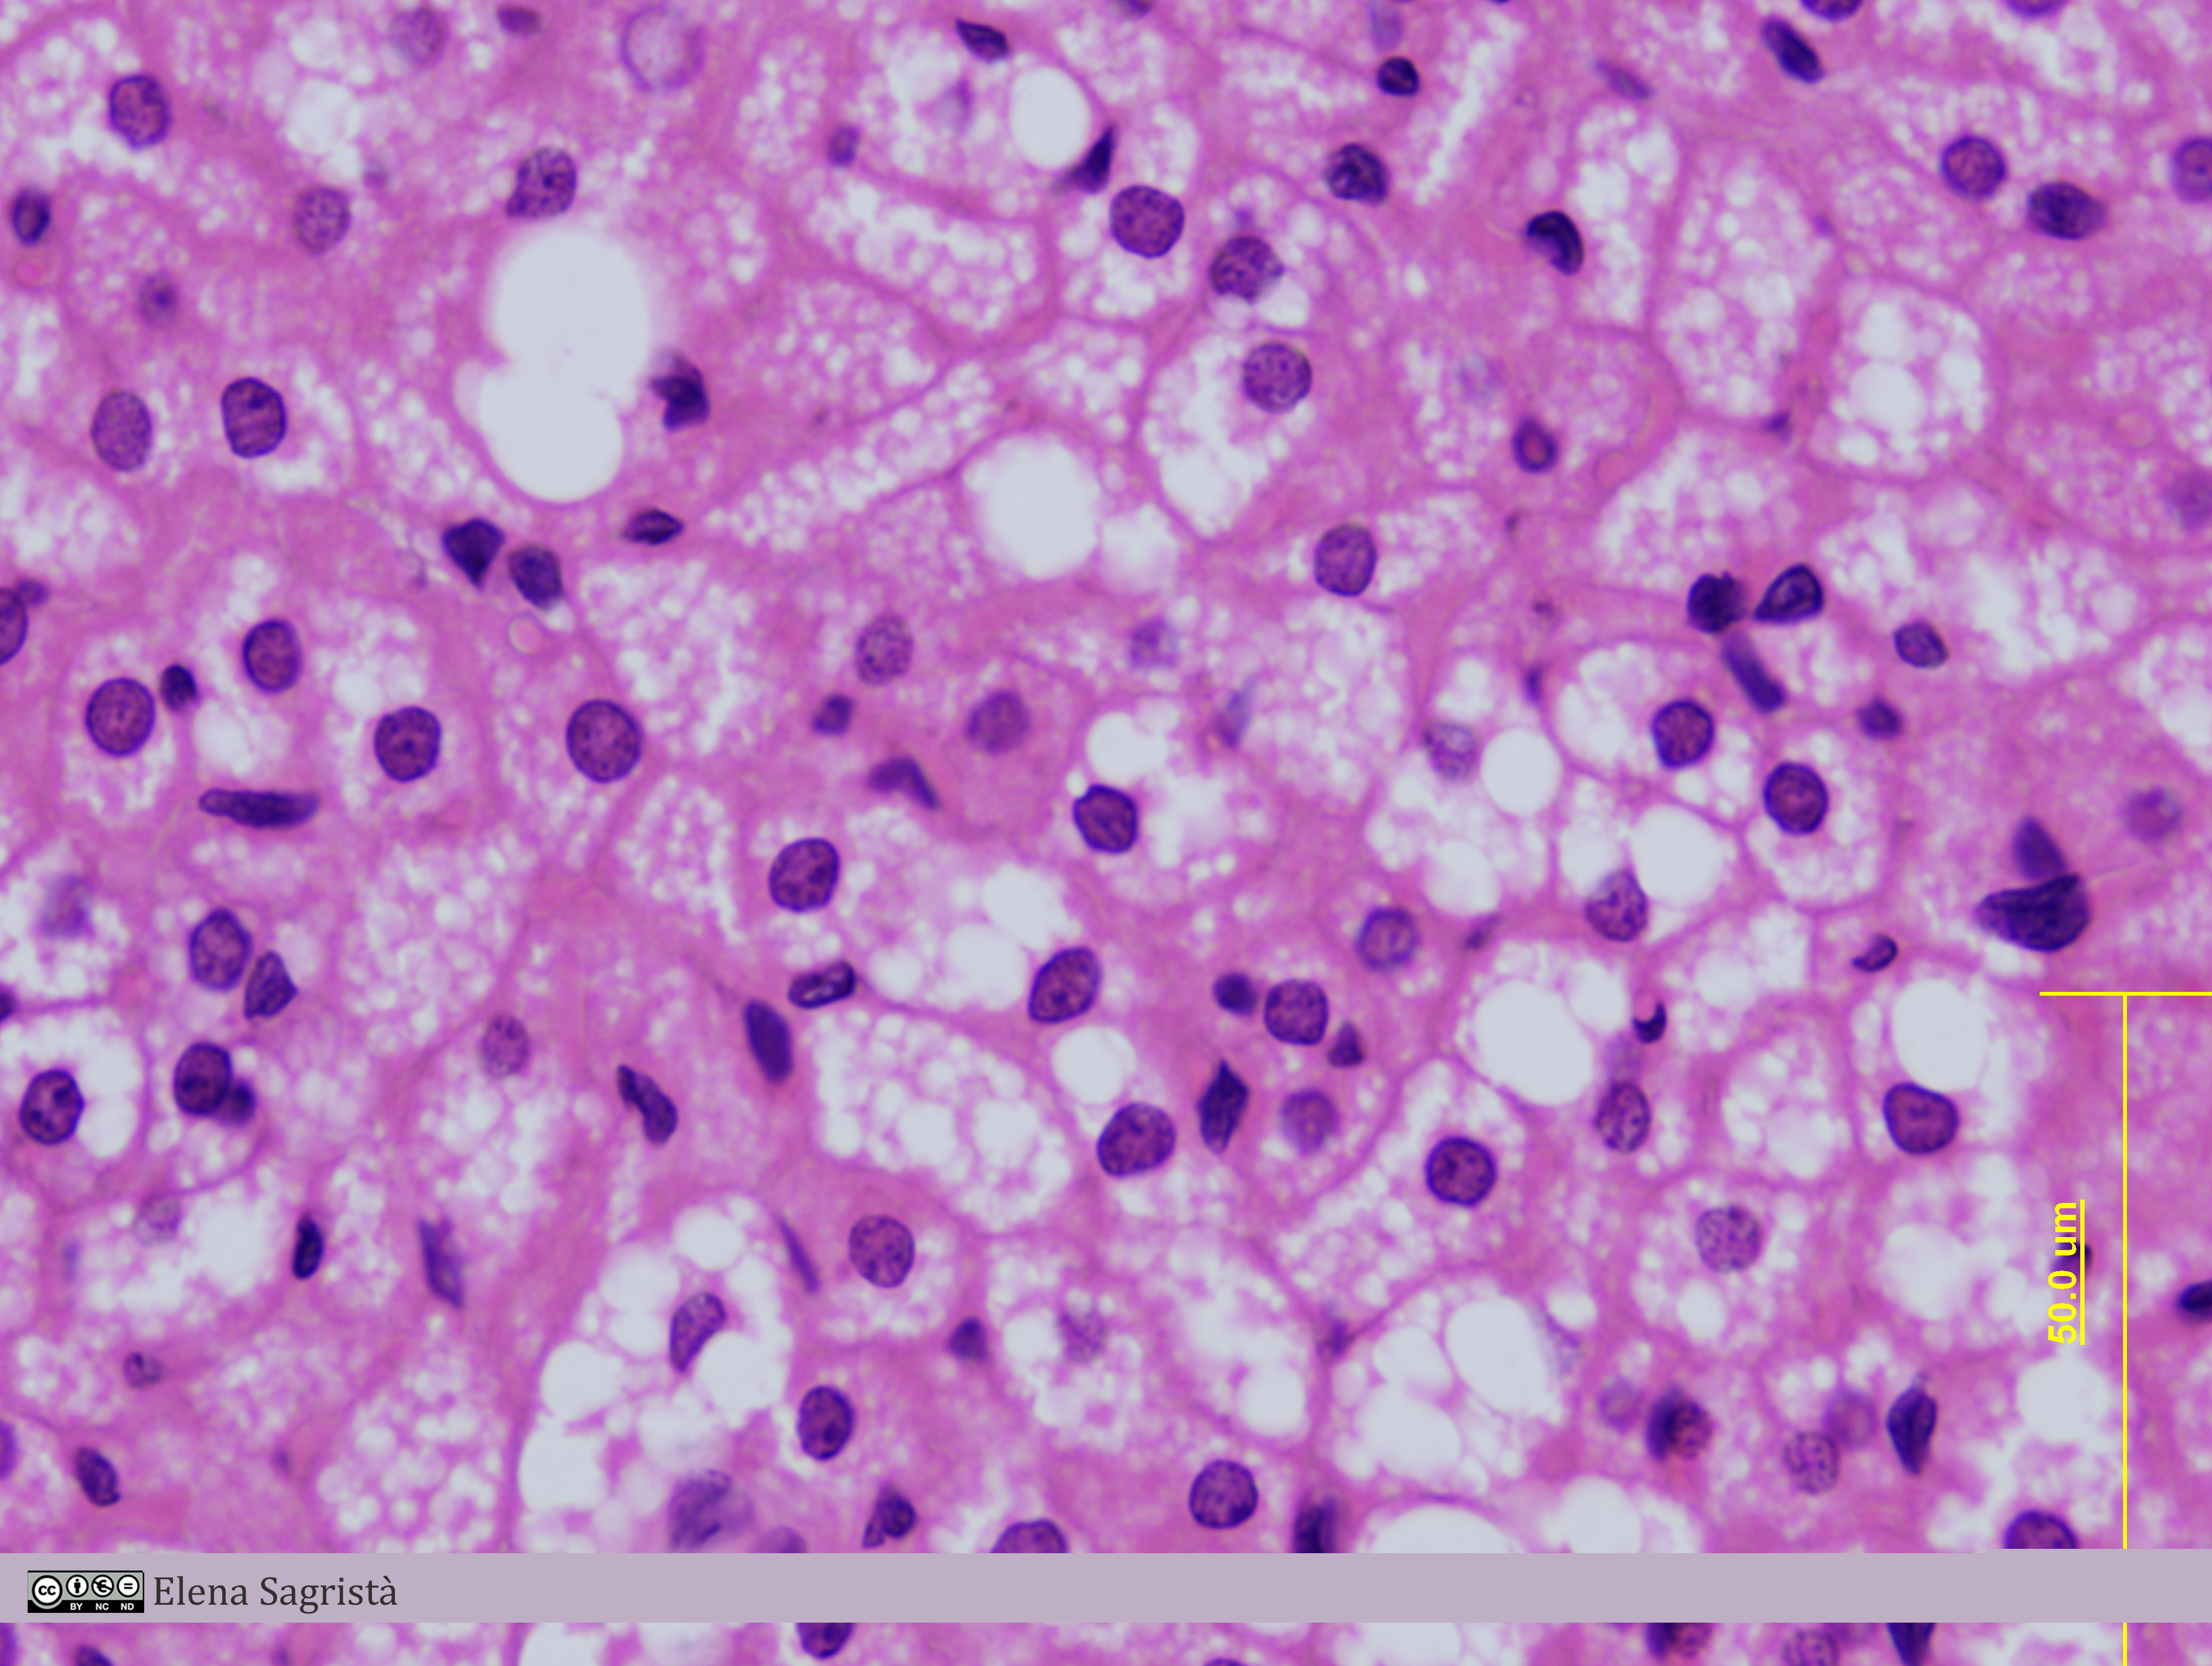

Histologia imatges: 03 Teixit adipós

Imatges de preparacions histològiques de Teixit adipòs. Microscopia òptica.